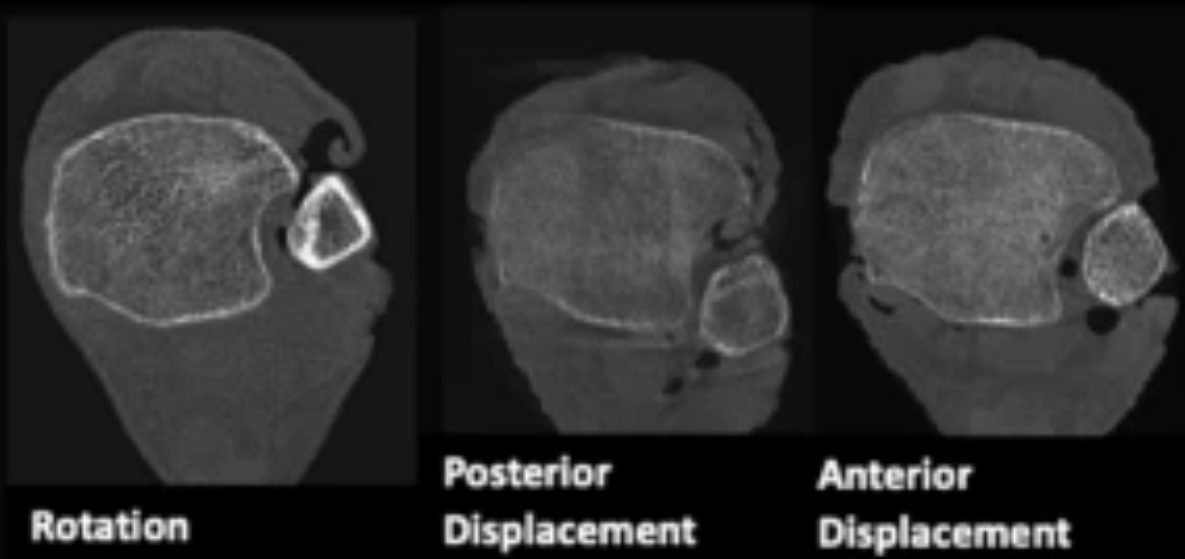

Рис. 14. Положение малоберцовой кости в боковой проекции

КТ превосходит стандартную рентгенографию в оценке целостности синдесмоза и способна выявлять подвывих синдесмоза, которую сложно визуализировать на обзорных рентгенограммах, особенно в неочевидных случаях. Возможность оценки обоих голеностопных суставов делает КТ предпочтительным неинвазивным методом оценки репозиции синдесмоза.

КТ-сканирование синдесмоза обычно проводится на уровне наиболее выступающей точки переднего бугорка большеберцовой кости. Повреждение синдесмоза диагностируется при межберцовом промежутке более 6 мм или расширении более 2 мм по сравнению с контралатеральной стороной. Повреждение с расхождением 2–3 мм может быть подтверждено на фронтальных КТ-срезах.

Рис. 15. Тибиофибулярная линия Гиффорда (TFL) на аксиальных срезах КТ и МРТ. Линия проводится вдоль переднелатеральной кортикальной поверхности малоберцовой кости. Расстояние от переднего бугорка Тилло-Шапута до TFL не должно превышать 2 мм. Параметр чувствителен к ротационной нестабильности.

КТ с нагрузкой (weight-bearing CT, WBCT) обладает дополнительным преимуществом — динамической оценкой синдесмоза: при нагрузке выявляются значимые латеральная трансляция и наружная ротация малоберцовой кости относительно вырезки.

В последние годы WBCT стала ведущим инструментом диагностики субклинической (subtle) нестабильности синдесмоза — той, которую не удаётся выявить стандартными методами. Наиболее перспективным направлением является трёхмерный волюметрический анализ: объёмные измерения синдесмоза на протяжении 5 см проксимальнее плафона большеберцовой кости продемонстрировали площадь под ROC-кривой 0,96 с чувствительностью 90% и специфичностью 95% (Ashkani Esfahani et al., 2022). Трёхмерное картирование расстояний (3D distance mapping) на WBCT показало наибольшую диагностическую точность в первых 1–3 см вырезки с AUC 80,9–83,0% (Krähenbühl et al., 2025). Эти данные свидетельствуют о том, что 3D-волюметрия на WBCT может стать новым стандартом диагностики повреждений синдесмоза, особенно в клинически неоднозначных ситуациях.